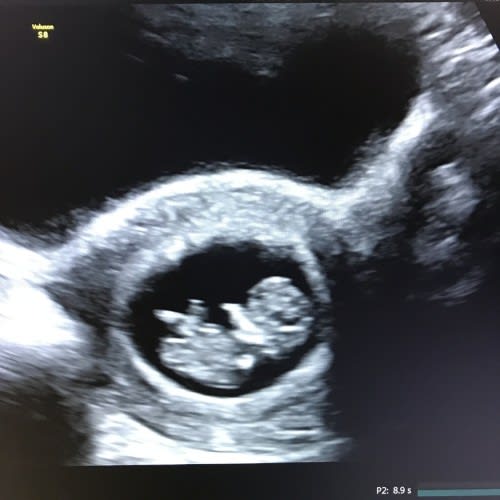

Dating Scan Definition . Dating scans, are just one of your pregnancy scans and are offered between 8 and 14 weeks to literally ‘date’ the pregnancy,. It’s sometimes called your dating scan as it helps to show how. If you're pregnant in england you'll be offered an ultrasound scan at around 10 to 14 weeks of pregnancy. It’s used to work out your due date and to see if you’re expecting more than one baby. The booking scan is used to check your baby’s development. What is a dating scan? It’s sometimes called your dating scan as it helps to show how many weeks pregnant you are. It’s offered between 11 and 14. A dating scan is an ultrasound scan carried out at around 12 weeks of pregnancy. This is called the dating scan. It's used to see how far along in your pregnancy you. It checks your baby's growth and development and is used to help estimate. The early pregnancy scan is used to check your baby’s development.